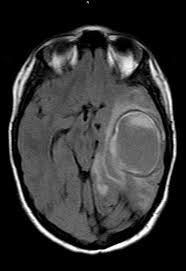

cavernoma

dilated vascular cavity lined by vascular endothelium

typically supratentorial

popcorn appearance on MRI, core can be hyperintense, dark rim on T2

can cause seizures, can bleed